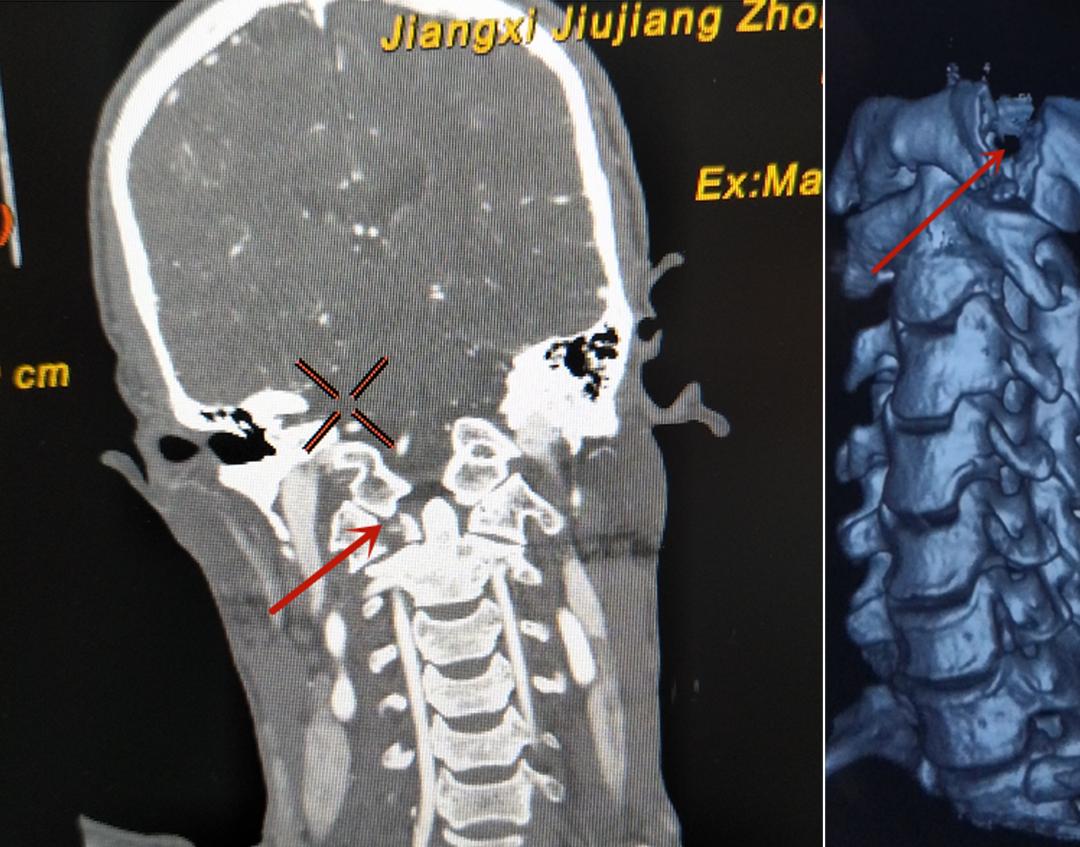

患者龚某,52岁,因工地工作时被高空坠物砸伤头部,导致头颈部疼痛且活动受限,入院就诊后,经查头颈部CT,结果显示,寰椎前后弓粉碎性骨折,并寰枢关节半脱位合并胸3,4,5压缩性骨折。寰枢关节是人体脊柱最重要的关节,这个部位的损伤可能出现瞬间死亡,或致后期颈椎严重病变。

由于患者损伤后颈部疼痛及活动受限,为避免患者症状进一步加重,保障患者功能及生命,需尽快为患者实施手术。在秉承医院“中学为体,西学为用”的精神下,脑病科专家组经讨论后,运用新引进的先进术中神经电生理检测技术,脑病科主任宗志涛带领团队在神经电生理检测下完成了寰椎骨折切开内固定术,术后给患者施以针灸、康复训练、中药等传统中医特色进行调理治疗,患者术后恢复良好,颈部疼痛有效缓解,且无明显肢体及功能障碍,术后3天可下床活动,为患者顺利康复打下了良好基础。